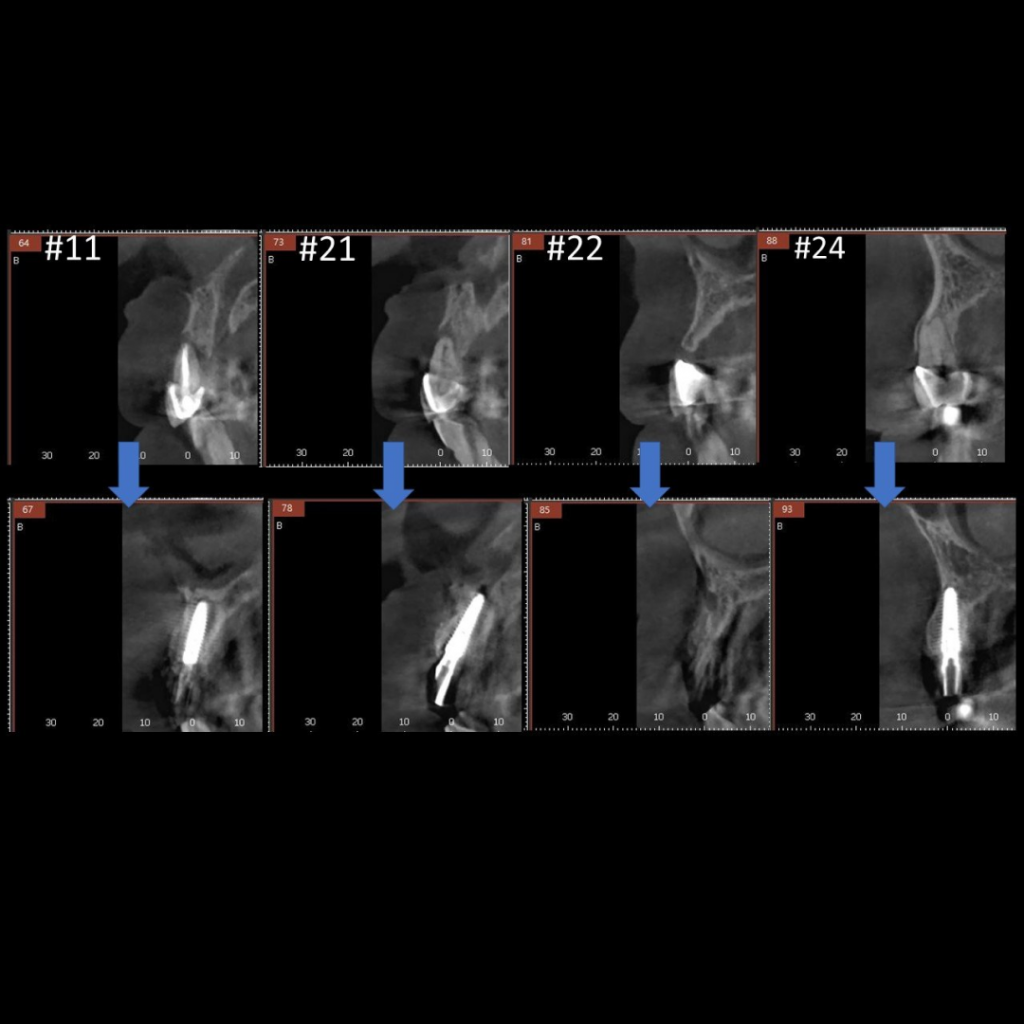

- Удаление несъемного мостовидного протеза по причине подвижности во фронтальной области верхней челюсти с диагнозом "Хронический генерализованный парадонтит и множественный кариес"

- Проведение имплантации AnyRidge с немедленной нагрузкой

- Заполнение костных дефектов смесью из костного материала TI-oss, аутокости пациента и обогащенной тромбоцитами плазмой PRP